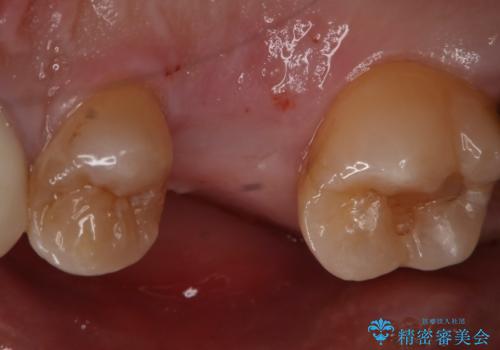

- 右上6番の歯の欠損部の治療を希望され来院された患者様です。

インプラント治療を希望されたので、インプラントとセラミッククラウンでの治療を計画しました。